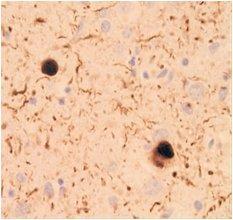

Immunohistochemistry

Species: Human (Dementia with Lewy bodies)

Site: Brain

Data by courtesy of

Dr. Iwatsubo, Graduate School of Medicine, The University of Tokyo